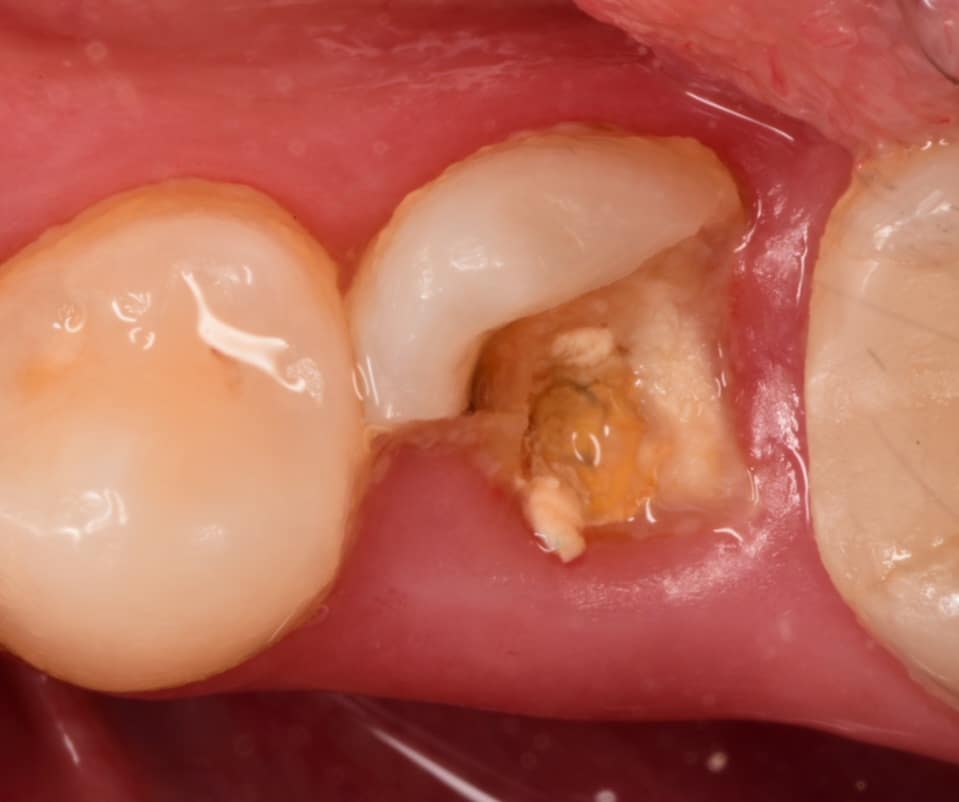

Buccal view

Step by step starting DME

Immediate after DME , gold standard clearfil SE bond used, RC with flowable composite from GC, Ribbond and ever x flow covered by composite for core building